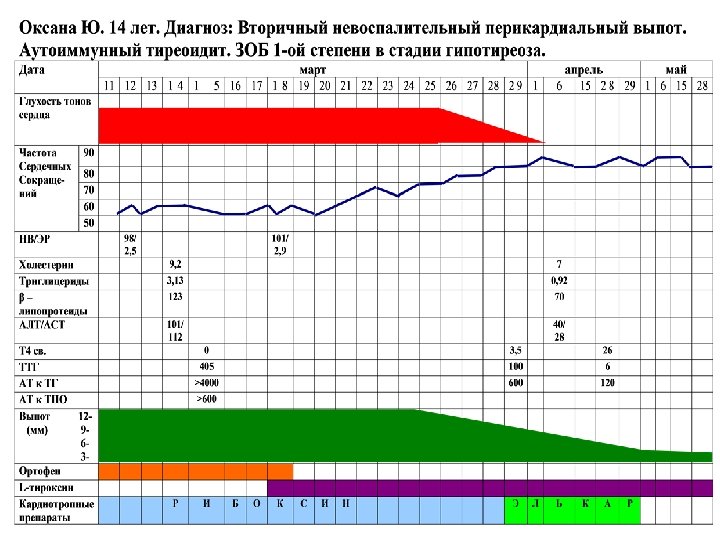

Рентгенограмма грудной клетки Оксаны Ю. 14 лет

ЭКГ Оксаны Ю. 14 л. 14. 03. 05

ЭКГ Оксаны Ю. 14 л. 6. 05